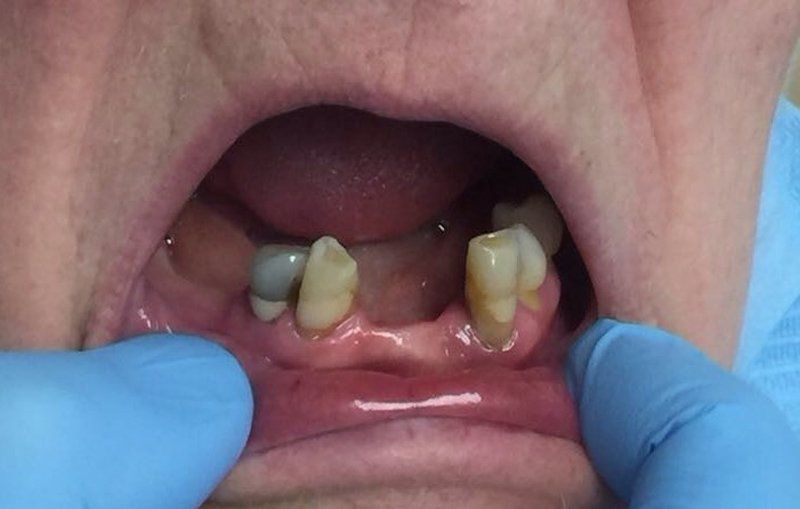

Riabilitazione protesica

Prima e dopo di riabilitazione con protesi totali su arcate superiore ed inferiore.

Button

Prima e dopo di riabilitazione con protesi totali su arcate superiore ed inferiore